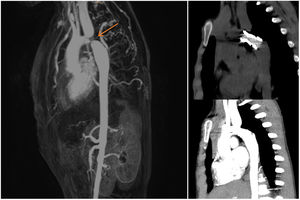

El electrocardiograma era normal para la edad de la paciente. Mediante ecocardiografía se observó estrechamiento aórtico inmediatamente distal al tercer tronco supraaórtico, con diámetro mínimo de 3mm, gradiente máximo de 50mmHg con cola diastólica, así como dilatación significativa de la arteria subclavia izquierda. Se solicitó angio-RM, en la que se confirmó CoAo grave en el ductus, con una estenosis estimada del 80% e importante desarrollo de circulación colateral a expensas de la arteria subclavia izquierda, que se confirmó dilatada (fig. 2).

Una vez confirmado el diagnóstico de CoAo, se decidió corrección percutánea. Se realizó angioplastia con colocación de stent CP montado sobre balón de 12mm y sobredilatación con balón de 14mm, con excelentes resultados. La evolución fue favorable, con desaparición de los episodios de cianosis (fig. 1). En el control radiológico al mes (angio-TAC), se objetivó que el stent seguía normoposicionado en el istmo aórtico, permeable y con buen calibre (fig. 2). Evolutivamente, la dilatación de la subclavia izquierda había disminuido, aunque persistía dilatada, mientras que se objetivó disminución significativa del calibre de las arterias intercostales y mamarias internas.